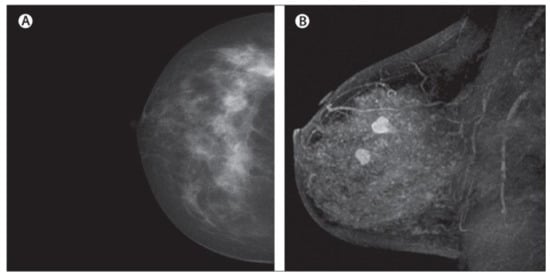

2.1. Mammograms (MMs)

The advantages of mammograms, such as being cost-effective to detect tumors in the initial stage before development, mean that MMs are the most promising imaging screening technique in clinical practice. MMs are generally images of breasts produced by low-intensity X-rays (Figure 1) [33]. In this imaging modality, cancerous regions are brighter and more clear than other parts of breast tissue, helping to detect small variations in the composition of the tissues; therefore, it is used for the diagnosis and analysis of breast cancer [34,35] (Figure 1). Although MMs are the standard approach for breast cancer analysis, it is an inappropriate imaging modality for women with dense breasts [36], since the performance of MMs highly depends on specific tumor morphological characteristics [36,37]. To deal with this problem, using automated whole breast ultrasound (AWBU) or other methods are suggested with MMs to produce a more detailed image of breast tissues [38].

For various tasks in breast cancer analysis, such as breast lesion detection and classification, MMs are generally divided into two forms: screen film mammograms (SFM) and digital mammograms (DMM). DMM is widely categorized into three categories consisting of full-field digital mammograms (FFDM), digital breast tomosynthesis (DBT), and contrast-enhanced digital mammograms (CEDM) [39,40,41,42,43,44]. SFM was the standard imaging method in MMs because of its high sensitivity (100%) in the analysis and detection of lesions in breasts composed primarily of fatty tissue [45]. However, it has many drawbacks, including the following: (1) SFM imaging needs to be repeated with a higher radiation dose because some parts of the image in SFM have lesser contrast and cannot be further improved, and (2) various regions of the breast image are represented according to the characteristic response of the SFM [19,45]. Since 2010, DMM has replaced film as the primary screening modality. The main advantages of digital imaging over file systems are the higher contrast resolution and the ability to enlarge the image or change the contrast and brightness. These advantages help radiologists to detect subtle abnormalities, particularly in a background of dense breast tissue, more easily. Most studies comparing digital and film mammography performance have found little difference in cancer detection rates [46]. Digital mammography increases the chance of detecting invasive cancer in premenopausal and perimenopausal women and women with dense breasts. However, it increases false-positive findings as well [46]. Randomized mammographic trials/randomized controlled trials (RMT/RCT) represent the most important usage of MMs, through which large-scale screening for breast cancer analysis is performed. Despite the great capability of MMs for early-stage cancer detection, it is difficult to use MMs alone for detection. Because it requires additional screening tests along with mammographic trials/RMT such as breast self-examination (BSE) and clinical breast examination (CBE), which are more feasible methods to detect breast cancer at early stages to improve breast cancer survival [38,47,48]. Additionally, BSE and CBE avoid tremendous harm due to MMs screening, such as repeating the imaging process. More details about the advantages and disadvantages of MMs are provided in Table 1.

Figure 1.

Example of breast cancer images using traditional film MMs. Reprinted/adapted with permission from [49]. 2021, Elsevier.